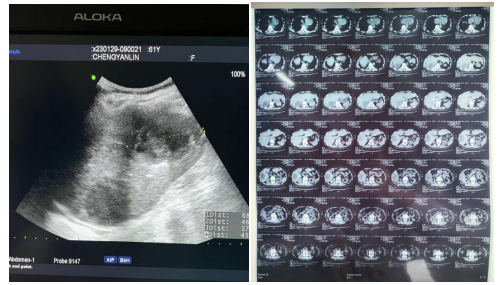

患者超声及CT检查影像

61岁的陈婆婆家住新洲,因右上腹持续性疼痛发热10天,伴有畏寒、高热,在当地91porn 行补液抗炎治疗,效果不佳,于1月29日到91porn (省中山91porn )阳逻院区就诊。经完善相关检查,超声检查提示:肝内多发无回声区(考虑肝脓肿)。得知检查结果后,陈婆婆及家属说出自己的顾虑:病痛难受、年龄大、术后伤口愈合迟缓、费用受限、家属不方便照顾等,经过普外科、超声影像科、麻醉科多学科会诊,在两院区一体化管理、学科深度融合的背景下,硚口本部超声影像科主任刘琨秉承着对专业的精益求精和不断创新精神和对病人减少创伤、减轻痛苦的原则,为陈婆婆制定了超声引导下肝脓肿穿刺引流方案。